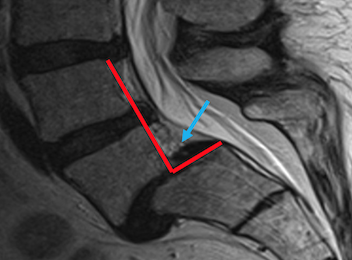

| Hernias de disco | Dolor de cuello, brazos |

| Dolor por desgaste de cartílago en rodillas, cadera y tobillo | Dolor de Espalda | Fibromialgía (dolor en todo el cuerpo) | Dolor posterior a cirugía de columna. |

En la valoración médica, se obtendrá un diagnóstico y la causa por la que se está ocasionando el dolor, se iniciara tratamientos analgésicos tomados vía oral, intramusculares, vía intravenosa o tratamientos potentes por infiltraciones, bloqueos nerviosos guiados por ultrasonido, terapia neural, aplicación de medicamentos bio-reguladores,toxina botulínica, se valorará el inicio de tratamientos para mejorar las emociones como ansiedad, tristeza o enojo. Asociado a tratamientos de rehabilitación física.